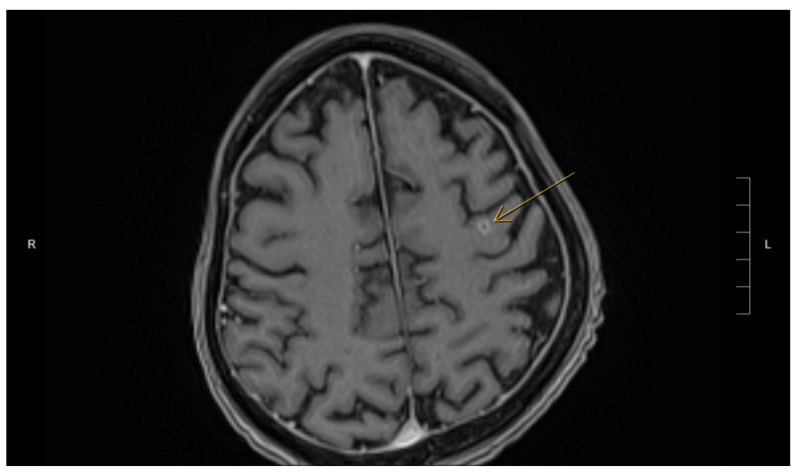

Disseminated nocardiosis is a rare, life-threatening infection, often misdiagnosed due to its resemblance to other conditions. We report a case of disseminated nocardiosis in a 62-year-old post-renal transplant patient presenting with pulmonary, hepatic, and pancreatic lesions. Despite multiple negative bacterial cultures, a histopathological examination of the liver revealed necrotizing granulomas with filamentous microorganisms, ultimately identified as Nocardia. This case highlights diagnostic challenges and the importance of integrating microbiological, pathological, and radiographical findings to manage and diagnose disseminated nocardiosis infections in immunocompromised individuals.